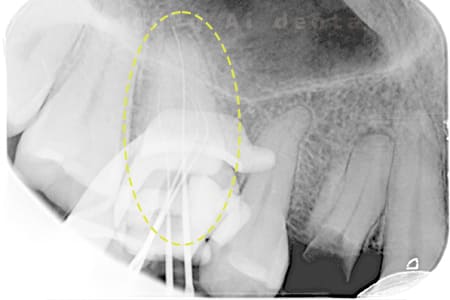

根管内の異物

- 原因

- 根管内異物(ファイル破折)による慢性根尖性歯周炎

- 治療期間

- 3ヶ月

- 治療内容

- マイクロスコープを使用した根管内異物除去並びにマイクロエンド

- 治療費用

- 121,000円(ファイル除去費用も込み)

他院で細い器具(ファイル)が根管内に破折した状態で、咬合痛を主訴に来院された患者様です。ファイルをマイクロスコープ下で除去し、根管治療を行ないました。